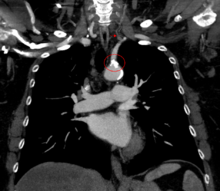

Diagnostic tests